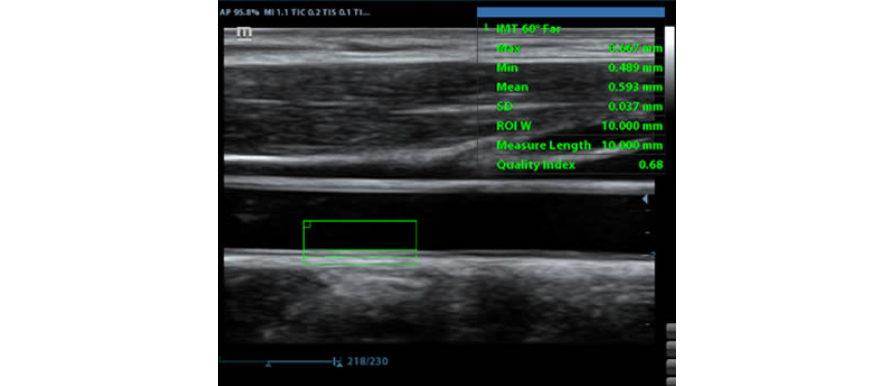

IMT (Intima-Media Kal?nl?k)

G├╝venilir karotid durum bilgisi sa?layan anterior ve posterior duvar kal?nl???n?n otomatik ?l?├╝m├╝.